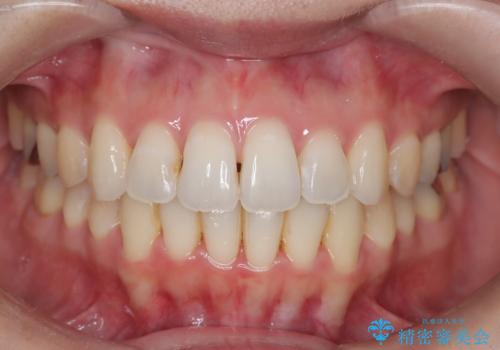

【抜歯インビザ】凸凹を綺麗になおしたい

叢生量が多いため、抜歯が必要となるため、ワイヤー矯正をお勧めしましたが、患者さんの希望によりインビザラインで治療を開始しました。途中でワイヤーリカバリーを必要とせず終了でき患者さんには満足していただけました。

ワイヤー矯正よりも期間がかかっています。